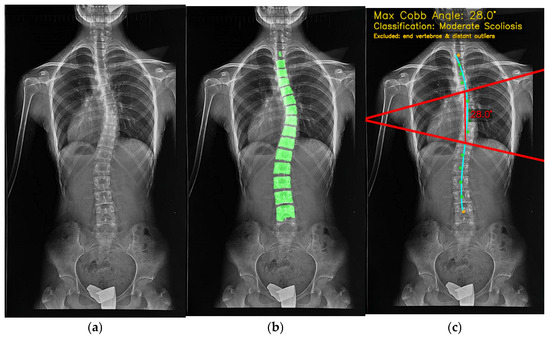

Vertebra Segmentation and Cobb Angle Calculation Platform for Scoliosis Diagnosis Using Deep Learning: SpineCheck

This study presents SpineCheck, a fully integrated deep-learning-based clinical decision support platform for automatic vertebra segmentation and Cobb angle (CA) measurement from scoliosis X-ray images. The system unifies end-to-end preprocessing, U-Net-based segmentation, geometry-driven angle computation, and a web-based clinical interface within a single [...] Read more.

This study presents SpineCheck, a fully integrated deep-learning-based clinical decision support platform for automatic vertebra segmentation and Cobb angle (CA) measurement from scoliosis X-ray images. The system unifies end-to-end preprocessing, U-Net-based segmentation, geometry-driven angle computation, and a web-based clinical interface within a single deployable architecture. For secure clinical use, SpineCheck adopts a stateless “process-and-delete” design, ensuring that no radiographic data or Protected Health Information (PHI) are permanently stored. Five U-Net family models (U-Net, optimized U-Net-2, Attention U-Net, nnU-Net, and UNet3++) are systematically evaluated under identical conditions using Dice similarity, inference speed, GPU memory usage, and deployment stability, enabling deployment-oriented model selection. A robust CA estimation pipeline is developed by combining minimum-area rectangle analysis with Theil–Sen regression and spline-based anatomical modeling to suppress outliers and improve numerical stability. The system is validated on a large-scale dataset of 20,000 scoliosis X-ray images, demonstrating strong agreement with expert measurements based on Mean Absolute Error, Pearson correlation, and Intraclass Correlation Coefficient metrics. These findings confirm the reliability and clinical robustness of SpineCheck. By integrating large-scale validation, robust geometric modeling, secure stateless processing, and real-time deployment capabilities, SpineCheck provides a scalable and clinically reliable framework for automated scoliosis assessment. Full article

Figure 1